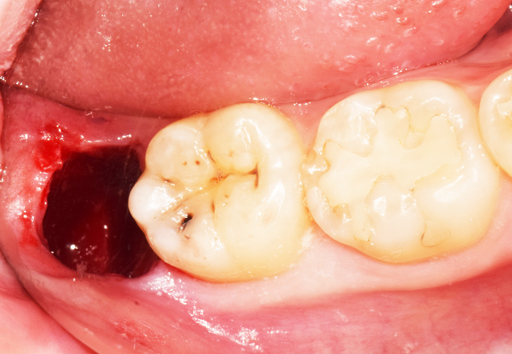

1. 피가 멈추지 않을 때 (지혈법)

발치 후 1~2일간 침에 피가 섞여 나오는 것은 정상이나,

입안에 피가 가득 고일 정도라면 적극적인 지혈이 필요합니다.